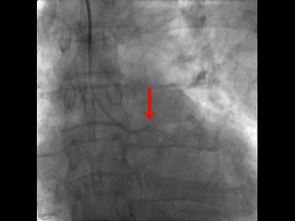

Judkins LのTFI(中)と比較してもIKARI L(右)のTRIのバックアップ力は強い

TRIとTFIの違い*

TRIは鎖骨下動脈の蛇行部位を通るのでバックアップが取りづらい

TRIとTFIの違い

• TRIは鎖骨下動脈の蛇行部位によってガイディングカテのバックアップが十分に取れない

• 鎖骨下動脈の蛇行部位でステントのプッシュ力がロスしてしまう

• プッシュが必要になりプッシュすると、鎖骨下動脈の蛇行部位の影響でバックアップが弱いガイディングカテが外れやすくなる(外れてしまう)